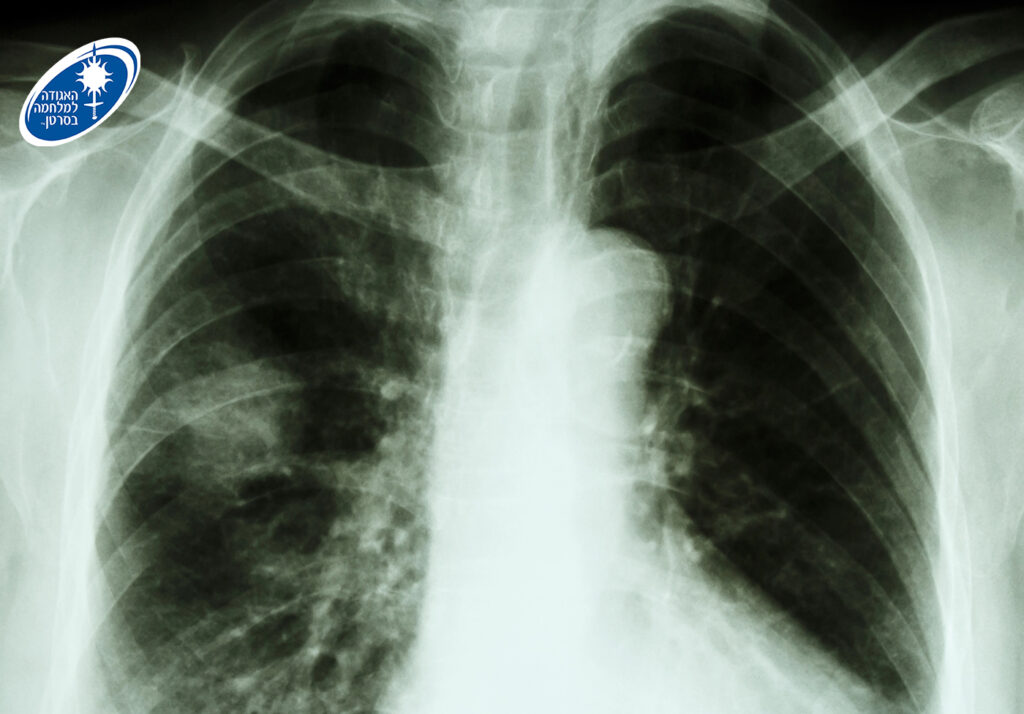

באגודה מעדכנים כי ניתן לגלות סרטן ריאה בשלב מוקדם ומציל חיים. כ-80% מהמקרים של סרטן זה קשורים בעישון, ולכן למעשנים כבדים בהווה או בעבר מומלץ לבצע מגיל 50, בדיקת CT במינון נמוך לגילוי מוקדם של סרטן הריאות. הבדיקה נכנסה לסל הבריאות ב-2025 לאנשים בני 75-64 עם היסטוריה של 20 שנות קופסה ומעלה, אם הם מעשנים בפועל או אם הפסיקו לעשן ב-15 השנים האחרונות.

מומחי האגודה למלחמה בסרטן מדגישים כי אם אחד מהתסמינים המפורטים לעיל נמשכים למעלה משלושה שבועות, חשוב להיבדק על ידי רופא משפחה. כל התסמינים עלולים להיגרם גם מעישון או ממחלות אחרות שאינן סרטן. לעיתים סרטן ריאה מאובחן באופן אקראי באנשים שאינם סובלים מתסמינים כלל, אך נבדקים בצילום או בסריקת ריאות לבירור בעיה אחרת.